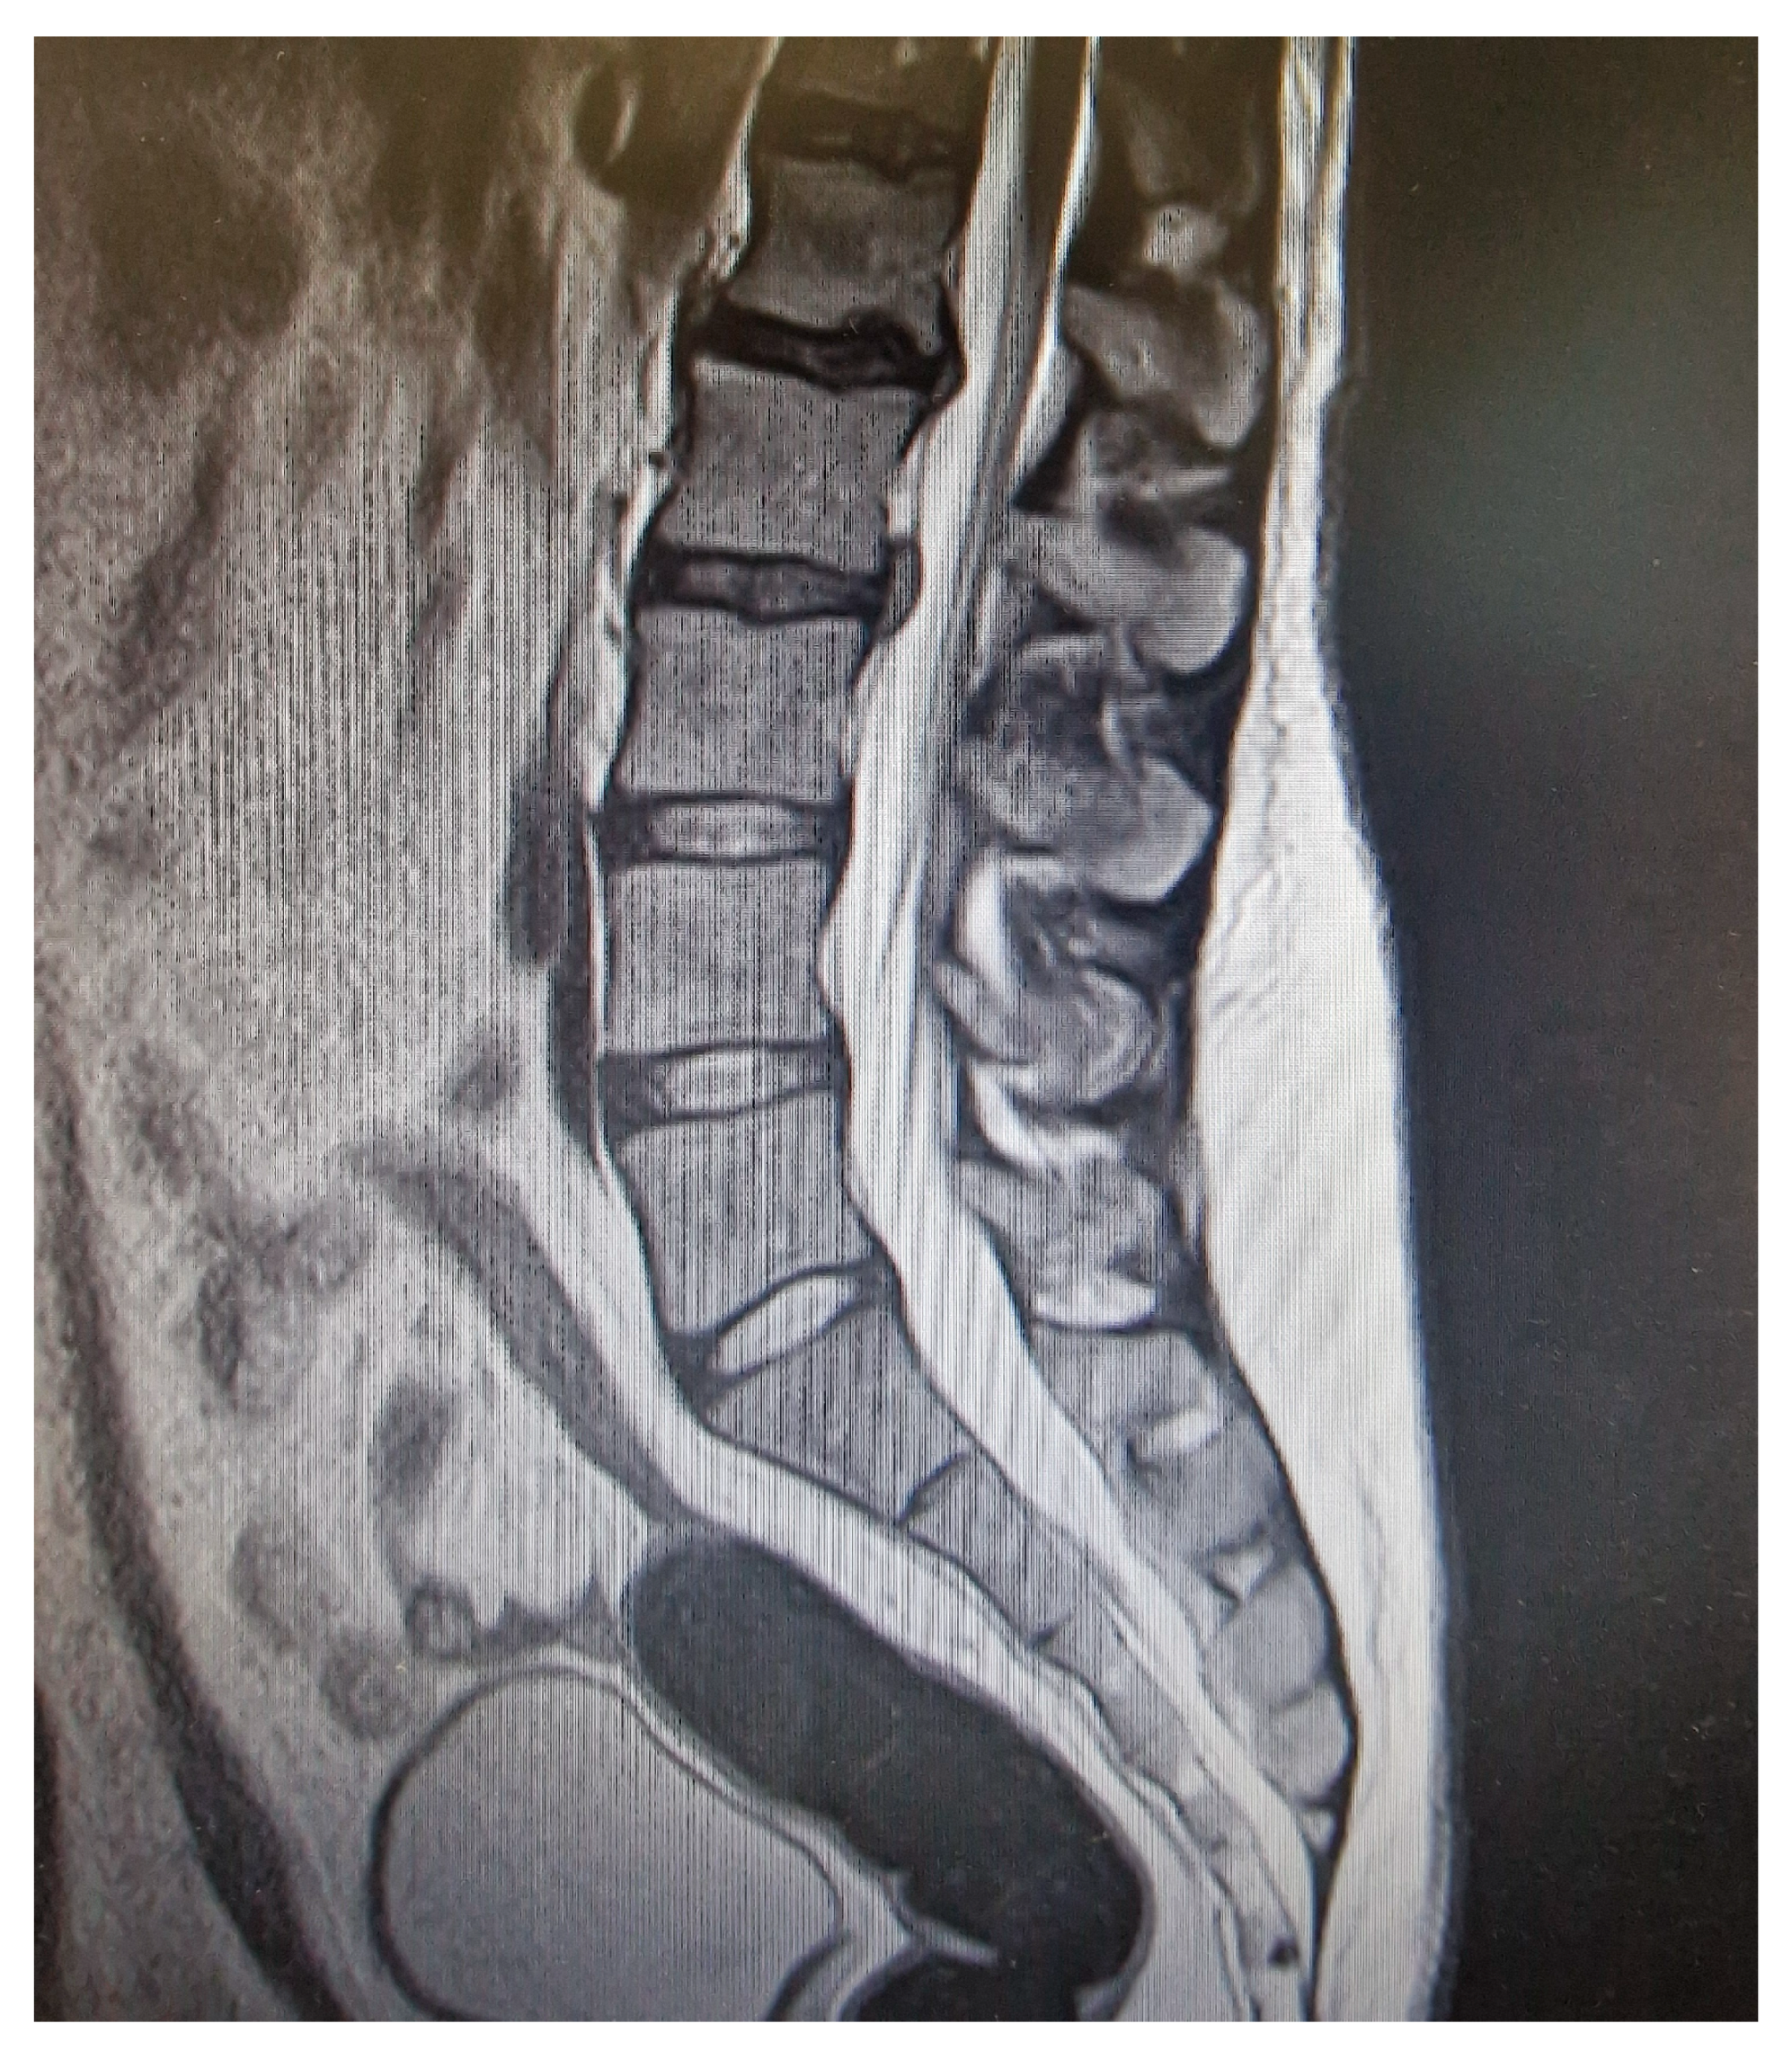

- MRI findings can be non-specific, particularly when performed after the initiation of therapy, highlighting the importance of early imaging and a strong clinical suspicion.